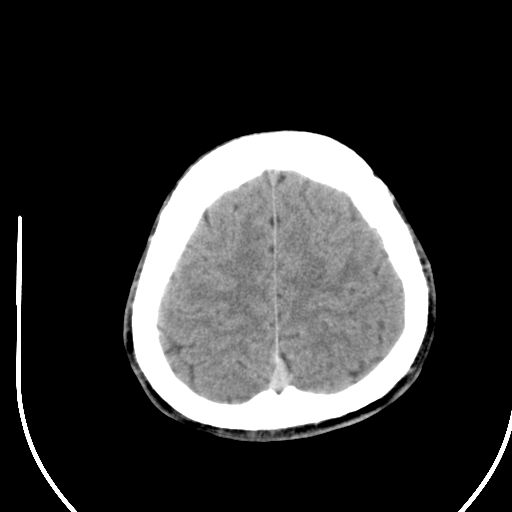

标题: CT28158:男,27Y。头痛数月,左顶叶血管瘤。 [打印本页]

标题: CT28158:男,27Y。头痛数月,左顶叶血管瘤。

海绵状血管瘤

考虑左顶叶海绵状血管瘤,建议mr检查。

左侧额叶海绵状血管瘤可能性大;建议行mri检查。

考虑血管畸形,因其周可见水肿,不除外感染性病灶。建议mri检查。